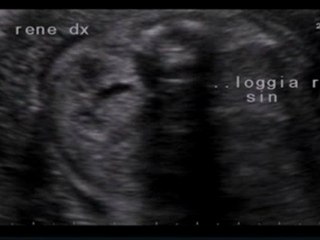

Litotrissia Percutanea Di Calcolosi Renale Sinistra + Ureterale Sinistra

Paziente con insufficenza renale acuta post-renale + monorene funzionale sinistro.